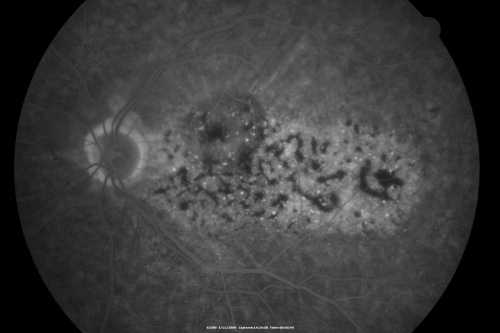

Bilateral Diffuse Uveal Melanocytic Proliferation - BDUMP - Paraneoplastic Syndrome

80-year-old man vision loss for one year.  He died about one year after these photos from Metastatic Poorly Differentiated Large Cell Carcinoma of unknown primary.  He was a smoker.